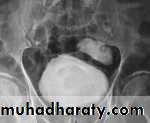

Radiograph from an excretory urogram demonstrates mild dilation of the right ureter associated with a simple ureterocele (u) that protrudes into the lumen of the bladder (B). The radiolucent wall of the ureterocele (arrowhead) is outlined by contrast within the ureterocele and contrast within the bladder lumen. The wall of the ureterocele is made up of the wall of the ureter and the bladder mucosa.

Bilateral ureteroceles. dilatation of the distal ureter as it enters through the bladder wall. This produces a typical “cobra head” deformity (arrows.